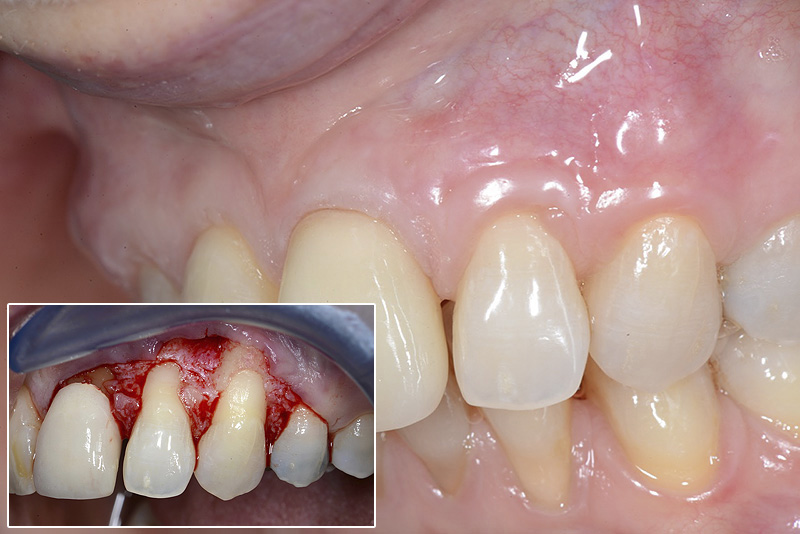

PREMESSA: in seguito all’estrazione dell’incisivo laterale superiore di destra, resasi necessaria per cause batteriche, si decide di affrontare il caso con il posizionamento di un impianto in sostituzione dell’elemento mancante dopo guarigione del sito infetto. Con tecniche rigenerative sia dei tessuti ossei mancanti a causa dell’infezione pregressa, sia dei tessuti gengivali che appaiono inizialmente troppo spostati in alto, si ripristina una corretta morfologia delle parabole (contorni) gengivali e delle papille interdentali (triangoli di gengiva tra due denti vicini).

Vengono utilizzati 2 tipi di provvisori: il primo, cementato ai denti vicini, viene utilizzato dal momento dell’estrazione del dente fino ad impianto osteointegrato (circa 6 mesi); il secondo, avvitato direttamente all’impianto, ha una funzione di prova estetica ma soprattutto di guida per la maturazione dei tessuti gengivali peri-implantari portandoli verso la maturazione completa prima di posizionare la corona finale in disilicato di litio.